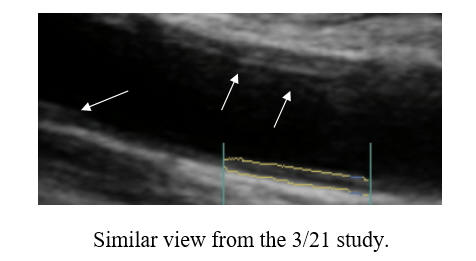

In early '23, cyclodextrin therapy was initiated, and after 60 doses IK was back in the pool, swimming full force. Hemorrhoidal irritation became and issue, prompting IK to switch to twice a week dosing. After roughly 180 doses (six boxes) through summer '24, IK's carotid study was repeated. The plaque progression identified between '10 and '22, was reversing! Twice a week maintenance cyclodextrin will be continued, along with IK's prior anti-atherosclerotic regimen, and we will repeat his carotid study in two years time.

Baseline Study in 3/21 Post-Cyclodextrin therapy in 3/23